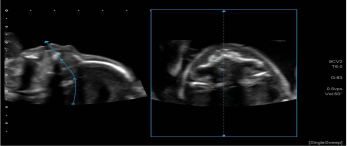

6. 智能融合&智能导航技术(Smart Fusion&Smart Navigation):智能融合技术可实现先前检查所获取的超声容积数据与实时2D超声图像之间的自动位置匹配,可用于介入治疗评估;也有CIVCO omniTRAX装置,实现超声图像和CT/MRI图像之间的自动位置匹配。

智能导航:利使用装有传感器的穿刺针,在超声图像上叠加穿刺针导航引导线,模拟显示穿刺针的路径和针尖的位置来实现导航,实时双屏幕针道显示,临床上利于穿刺介入。